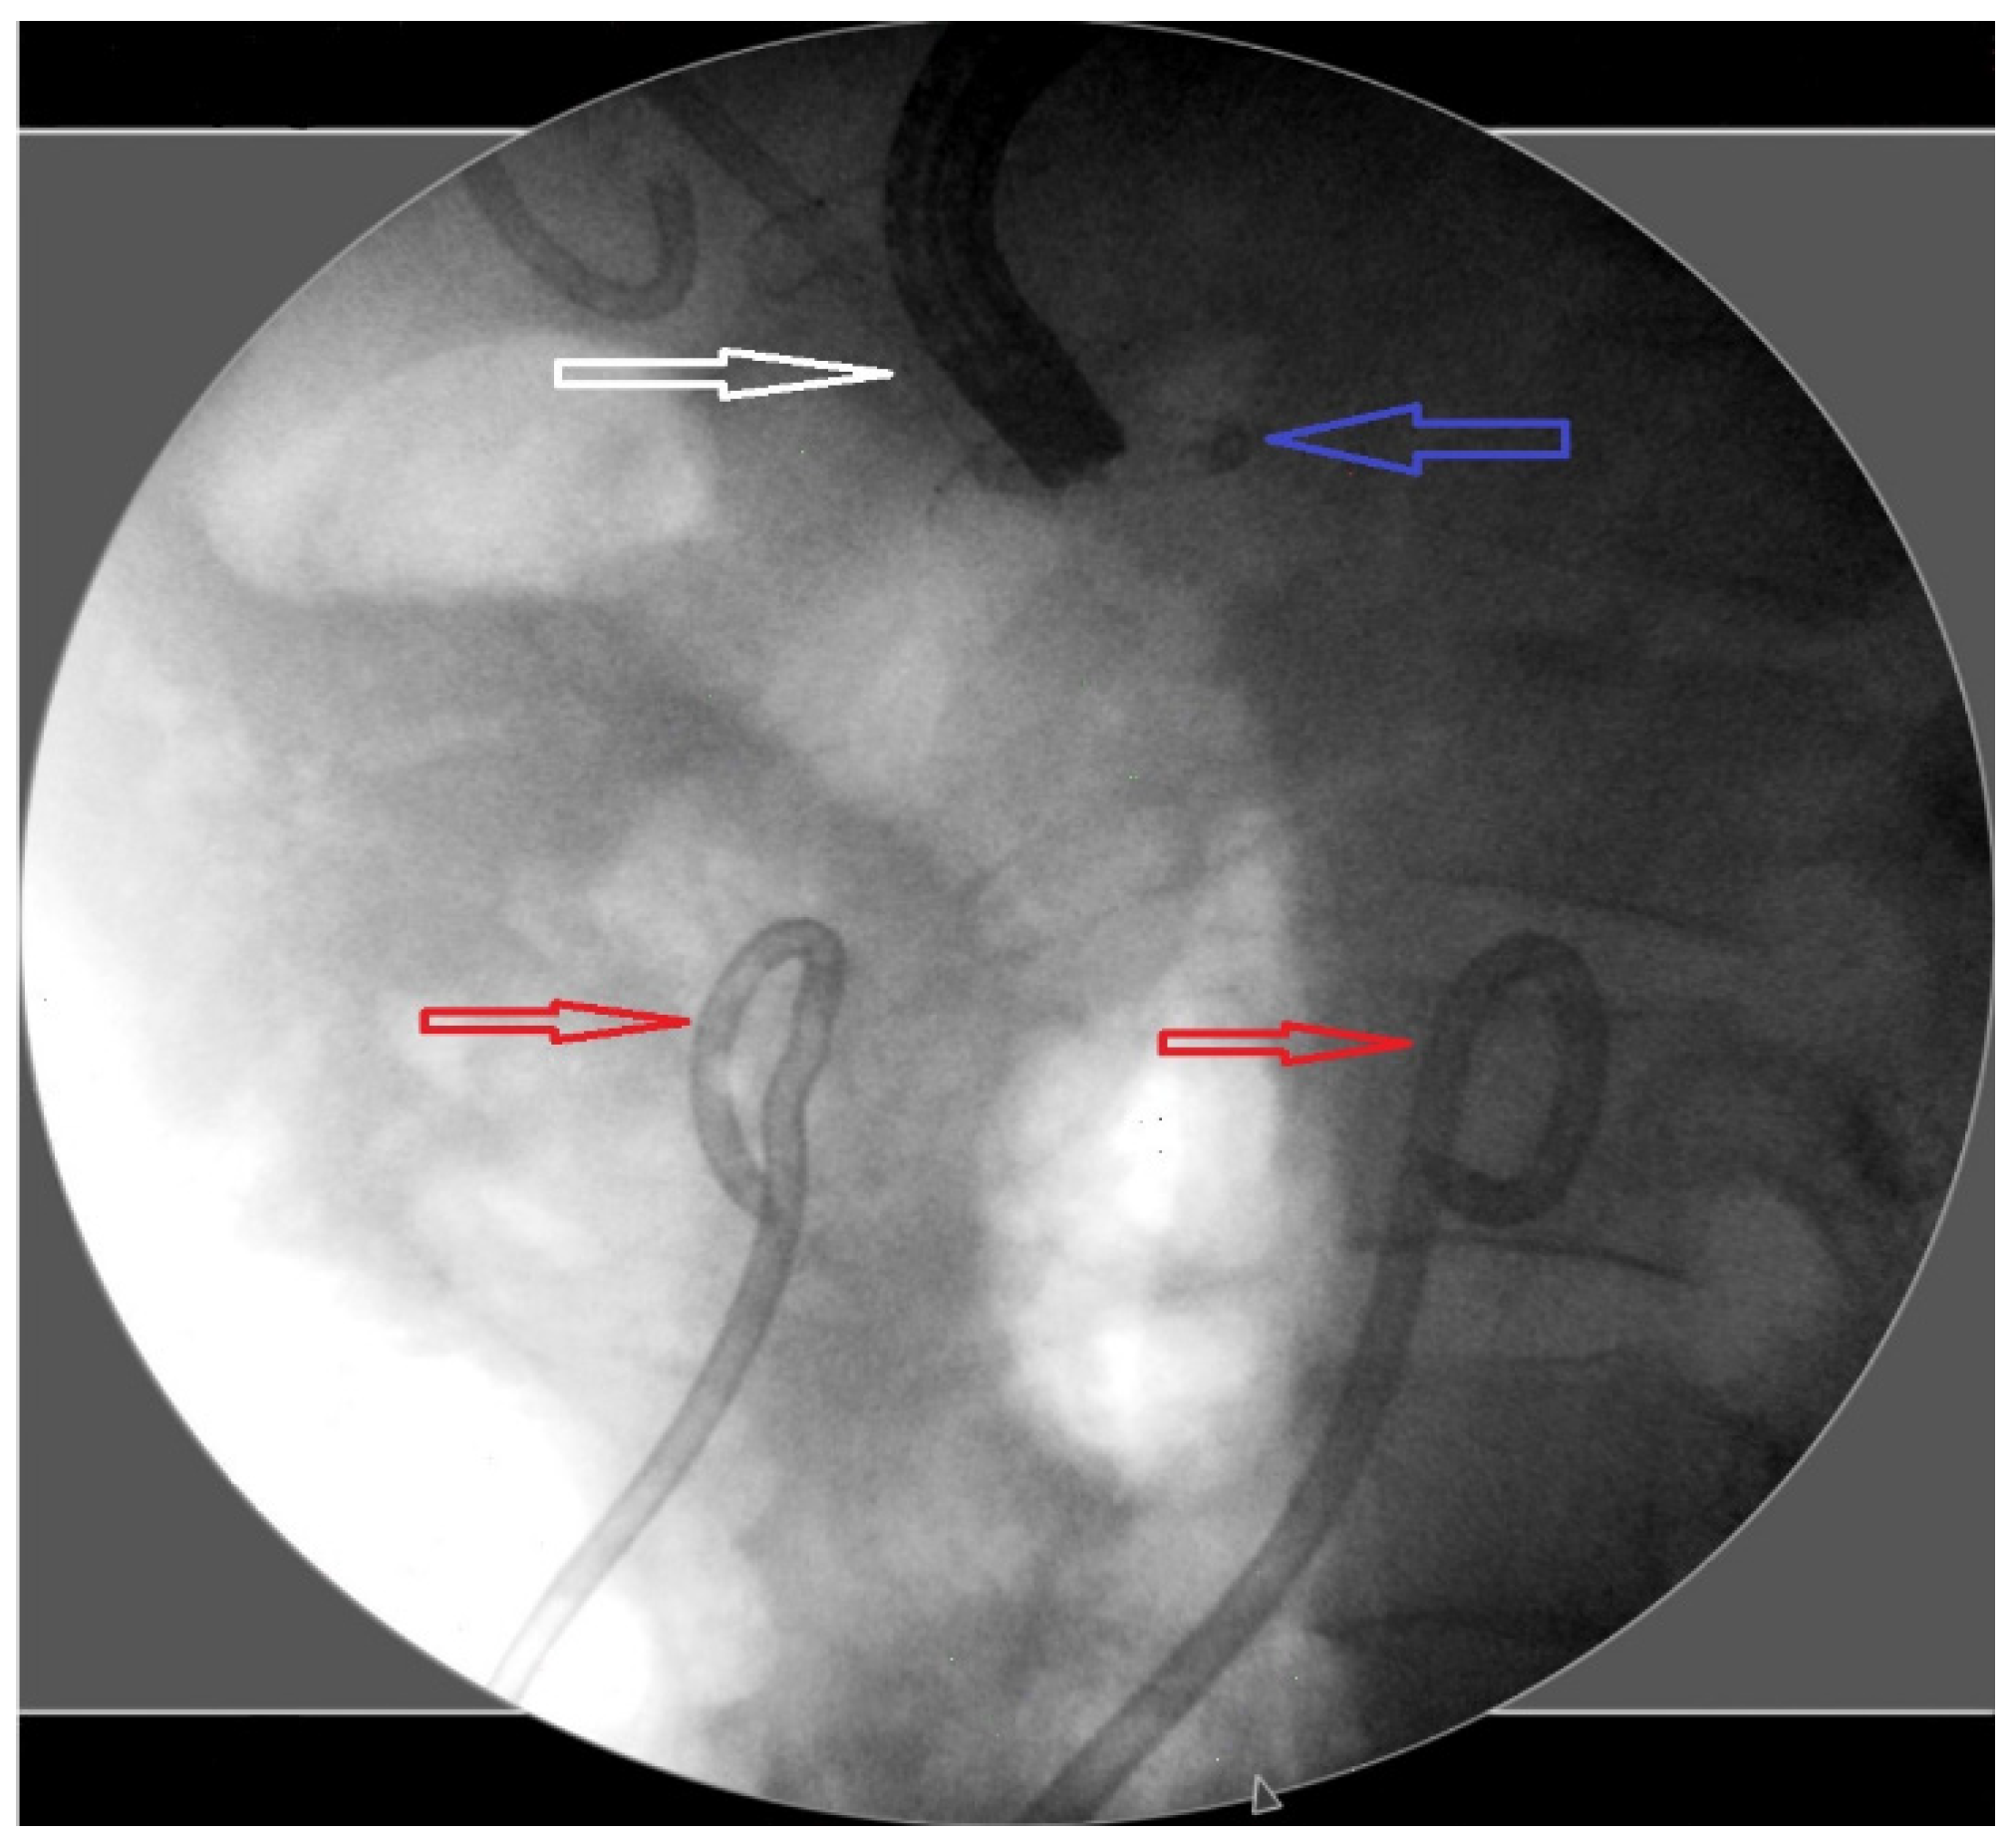

2. Materials and Methods

3.4. Outcomes of Complications, Recurrence, and Follow-Up